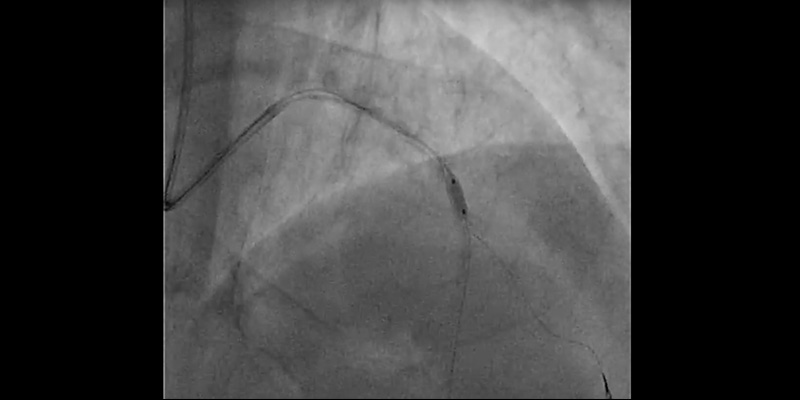

• Control angiography showed dissection at bifurcation involving the ostium of the first diagonal branch. With the help of a dual-lumen catheter, a second wire was placed into the diagonal branch.

• IVUS (OptiCrossTM IVUS catheter) showed plaque rupture after rotablation at different levels. However, a calcium ring of more than 270º was observed at the site of maximum plaque.

• For this reason, plaque modification was completed with a 2.5x6mm FlextomeTM Cutting BalloonTM.

• Finally, provisional stenting of mid LAD (2.75x24 mm Synergy stent) and post-dilatation with a NC EmergeTM (3.0x12 mm) showed a good result when confirmed with IVUS. Dissection on the diagonal was still present, with a TIMI 3 flow.